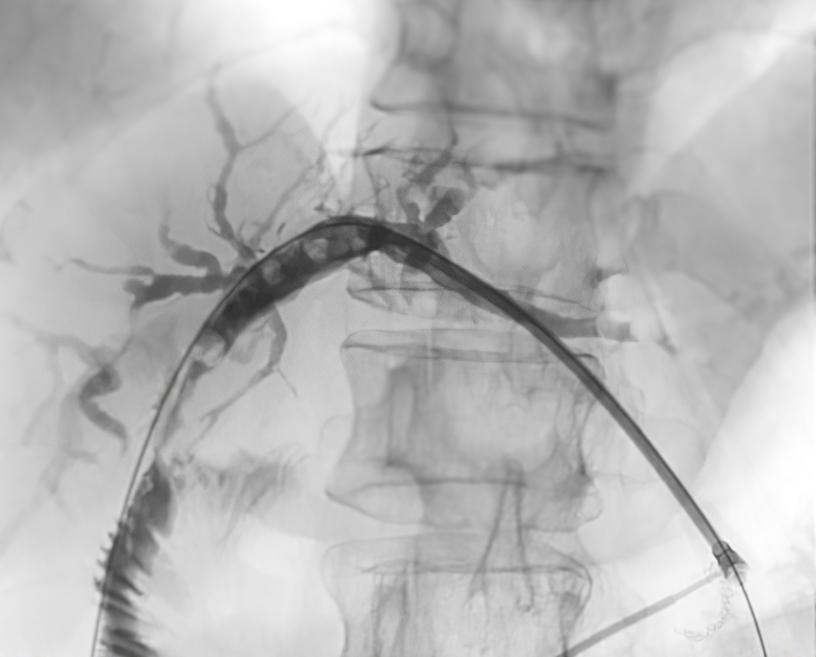

内镜下逆行胰胆管造影术:通过胃镜置入支架,以解除胰管或胆管狭窄,并引流胆汁或胰液,是胰管结石和狭窄的常用治疗方法。

图2 版权图片 不授权转载